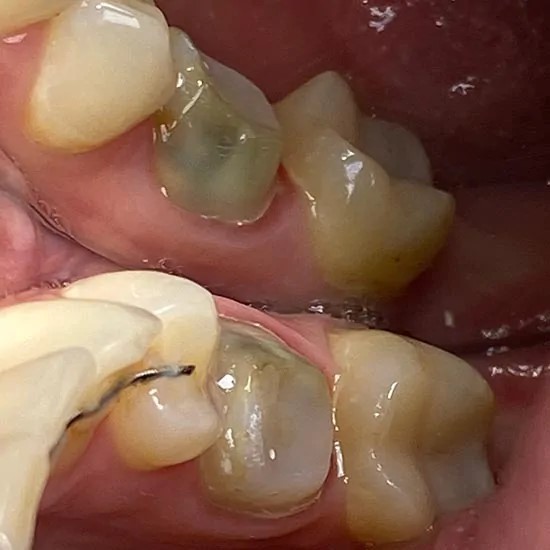

Установка металлокерамической коронки